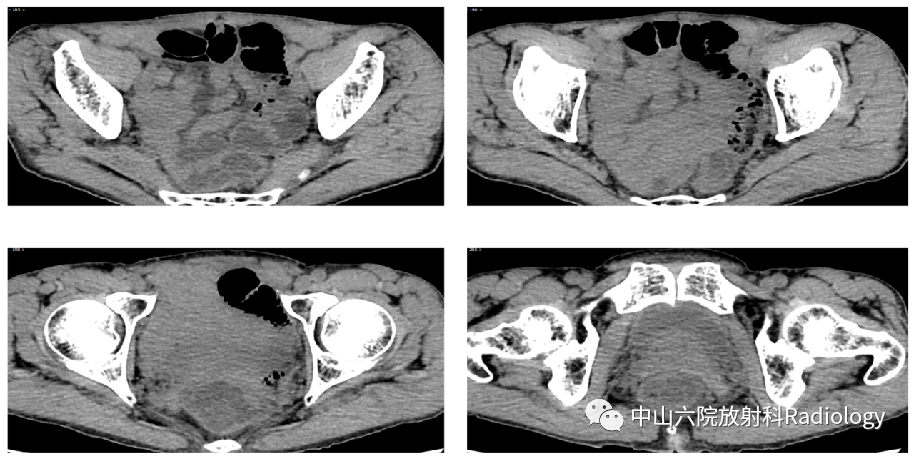

CT表现

平扫

平扫+增强